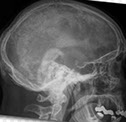

Lytic lesion of bone almost exclusively in kids, which can be multicentric, usually presenting c pain

- can be in any bone: skull, ribs, long bones

Imaging: variable, lytic, well-defined lesions

- can have a hole-in-hole appearance on skull x-ray

- may look malignant, c ill-defined infiltrative appearance

Micro: looks like an abscess at low power, but main thing is (of course) proliferation of Langerhan's cells c folded / groovy nuclei in loose clumps

- has variable number of eos, lymphos, plasma cells, and neuts

- may have eo abscess

IHC: (+) S100, CD1a confirms